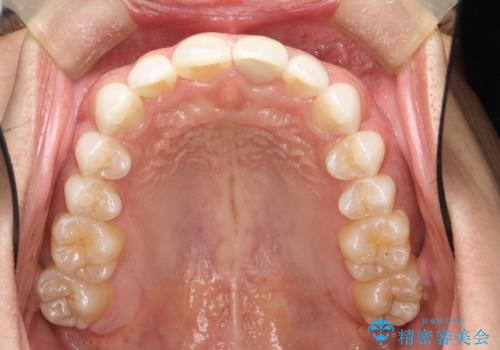

インビザラインによる矯正治療(非抜歯) 下の前歯の歯並びの改善

概ね1年弱で治療が完了しました。

前歯の大きな3次元的移動を可能にするために、当院独自の工夫を随所に盛り込み、狙い通りの治療結果を得られました。